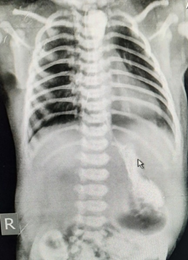

On examination, heart rate was 147/min, blood pressure was 75/50 mmHg, and respiratory rate was 52/ min, SPO2 was 97% with oxygen and capillary refilling time was <3 sec. with chest retraction. She had moderately increased secretions from mouth with bilateral conducted sounds. Feeding tube could not be negotiated into stomach. X ray showed coiling of infant feeding tube and large radiopaque shadow in the upper esophagus (Figure 1). Fact that child had accepted feeds well for initially 3 days without any discomfort, raised doubt in it being esophageal atresia. Contrast study was done which revealed large opacity from T2-4and trickling of contrast in stomach ruling out EA and esophageal perforation (Figure 2).

Figure 2 Contrast study showing radiopaque shadow from T2-4and trickling of contrast in stomach ruling out EA and esophageal perforation.